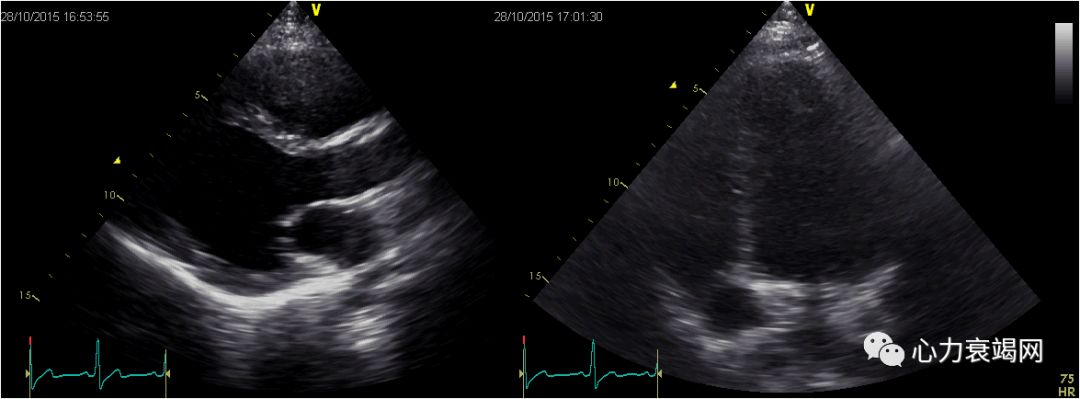

甲强龙40mg qdivgtt,CTX0.4g/w

四联抗结核:

- 异烟肼0.3g qd+利福平0.45g qd+吡嗪酰胺0.5g tid+乙胺丁醇0.75g qd

补钙、抑酸、保肝

胸闷明显好转、无咯血,可以平卧,平地活动不受限

限水每日1500ml、利尿(每日速尿60mgiv+螺内酯20mgqdpo)、扩血管(硝酸甘油泵入25mg/h)、补充电解质。

卡维地洛6.25mg Q12h,开博通6.25mg Q8h。

2个月后

激素及抗心衰治疗后